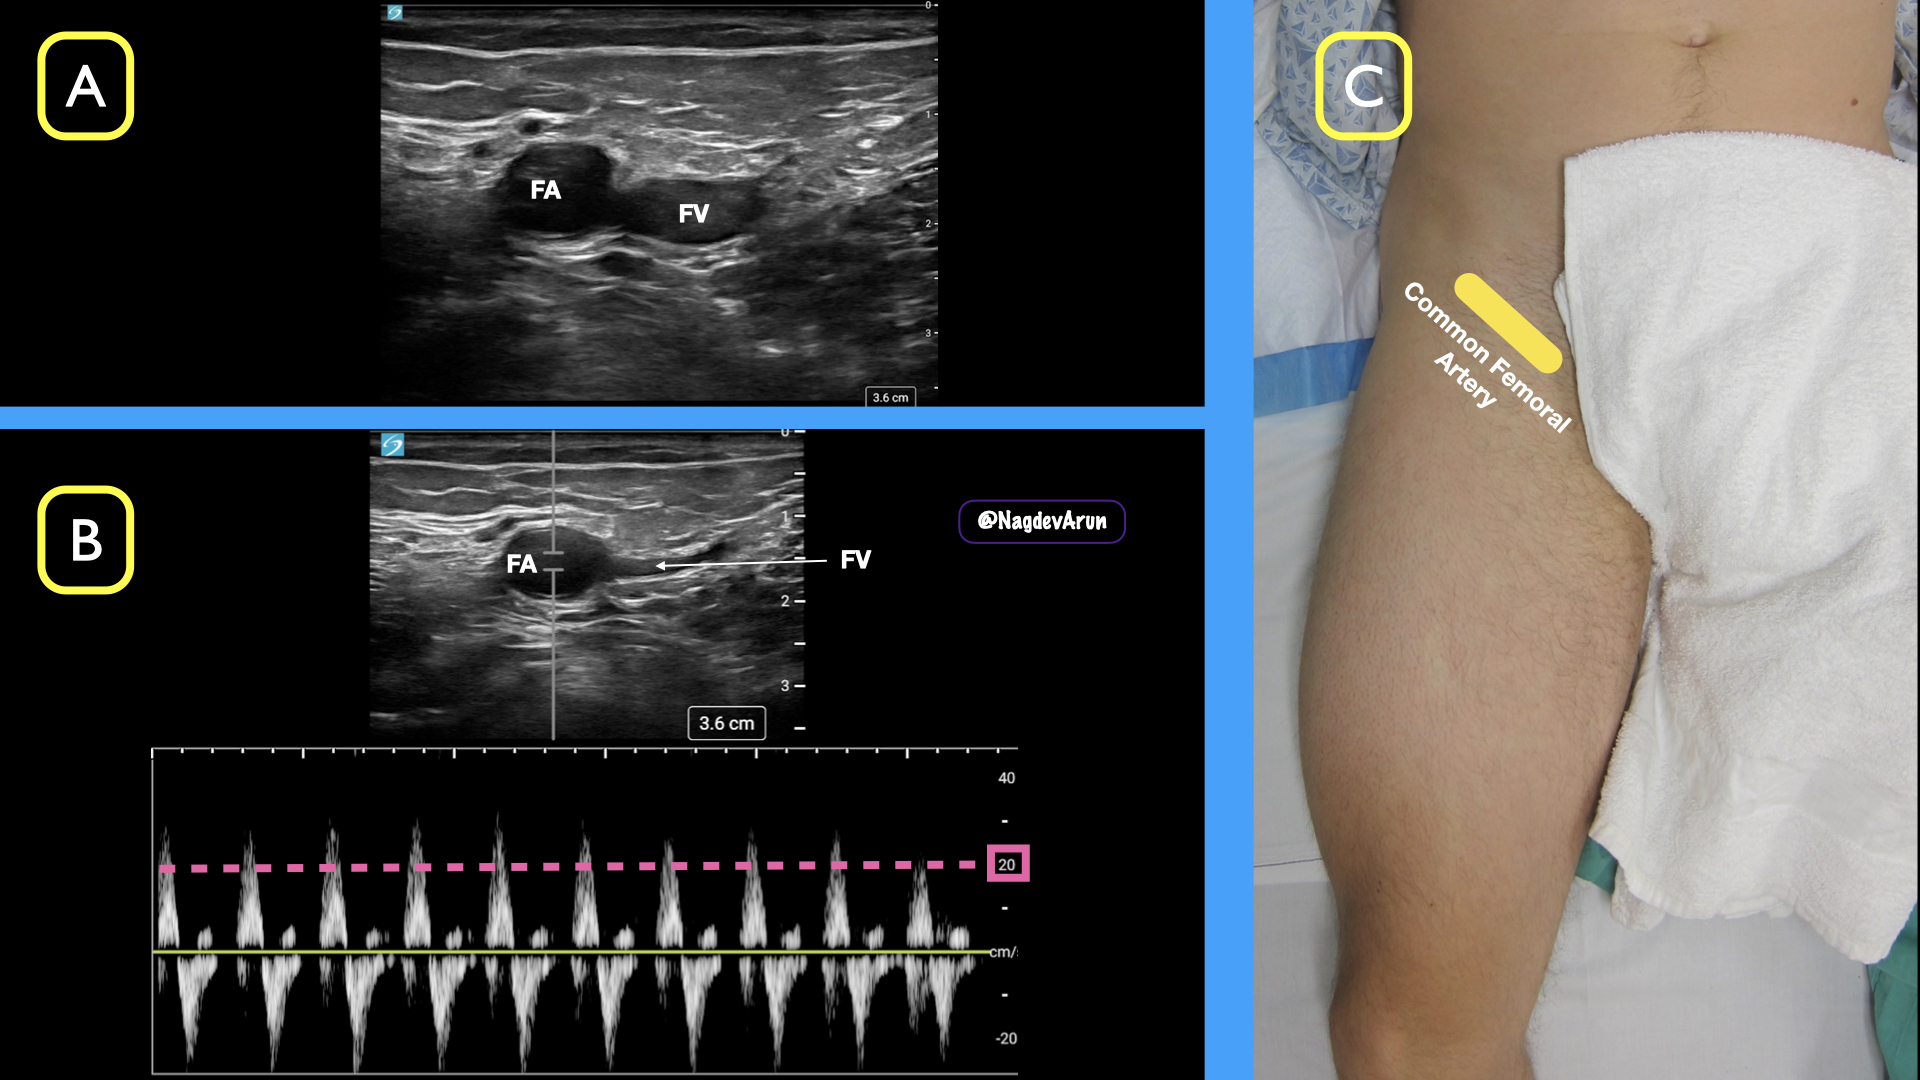

_rosc femoral ACEP 2 pics._002